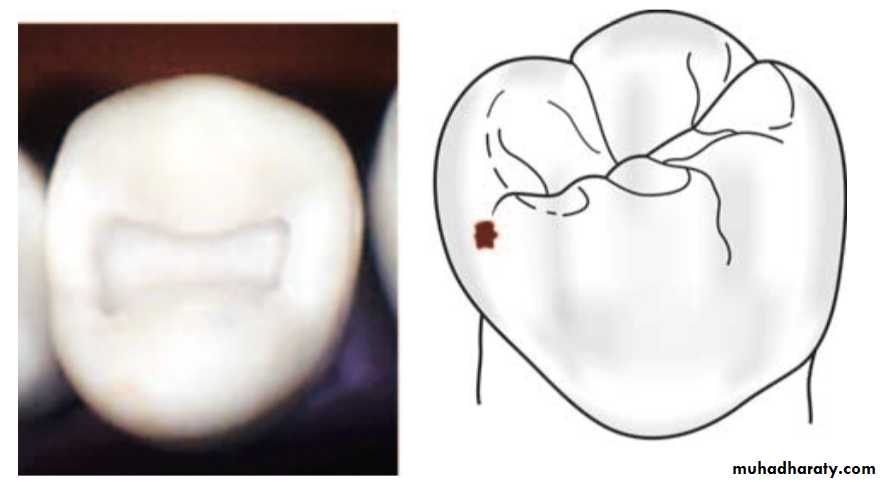

Class I–Pit and fissure preparationsoccur on the occlusal surfaces of premolars and molars, the occlusal two-third of buccal and lingual surface of molars, lingual surface of incisors and any other abnormal position